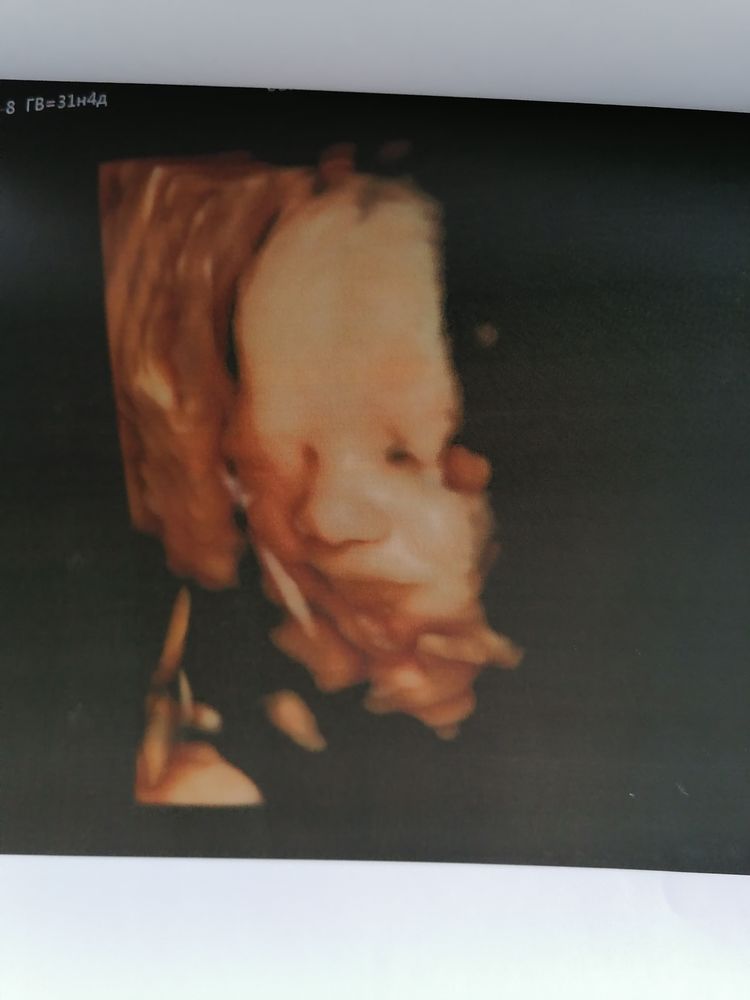

НЮША (ник в ИГ Visla79)

Все замеры делаются в 2D, а в течении УЗИ, если ребенка хорошо видно врач переключает на 3D.

Вот сын в 31 неделю.

НЮША (ник в ИГ Visla79), просто невероятно,уже настоящий человечище!)это конечно отличается от черно-белых фото)